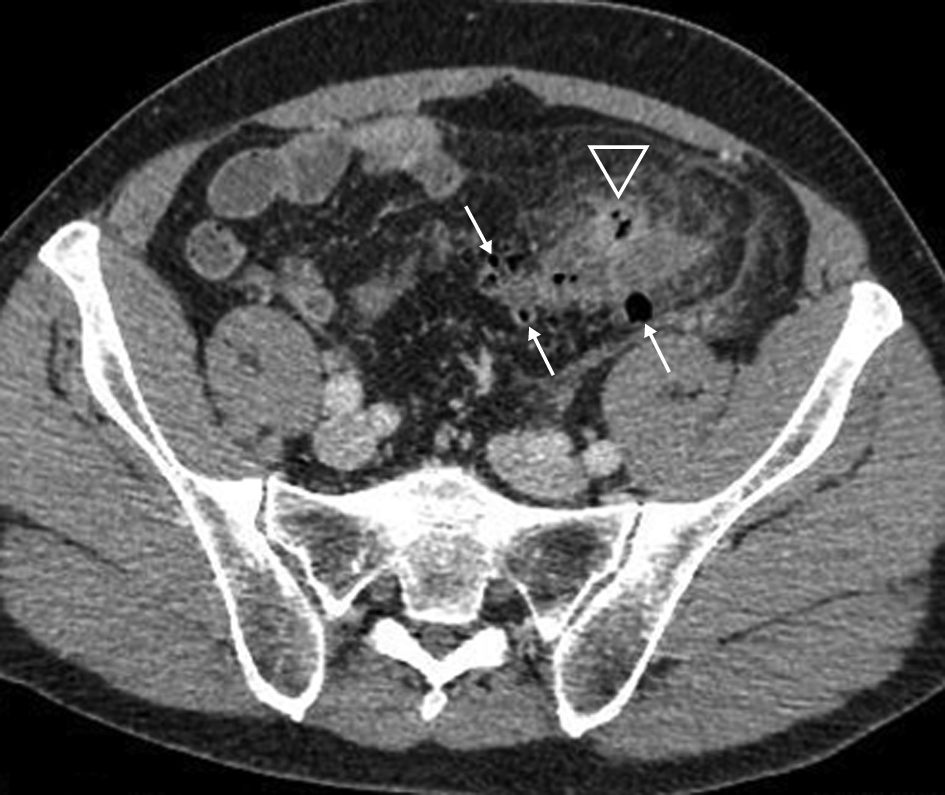

Les signes que l’on peut rencontrer dans la diverticulite sont l’épaississement de la paroi du côlon diverticulaire et/ou d’un diverticule, et, surtout, l’infiltration de la graisse autour du diverticule et autour de la paroi colique (figure 6.1). La présence d’adénopathies inflammatoires est possible ainsi qu’un épanchement intrapéritonéal réactionnel modéré.

Fig. 6.1 Diverticulite non compliquée.

Scanner au temps portal après injection intraveineuse de produit de contraste iodé. La paroi du côlon est épaissie. Il existe plusieurs diverticules (flèches fines). L’infiltration de la graisse périsigmoïdienne prédomine autour du diverticule antérieur (tête de flèche).

Source : CERF, CNEBMN, 2022.